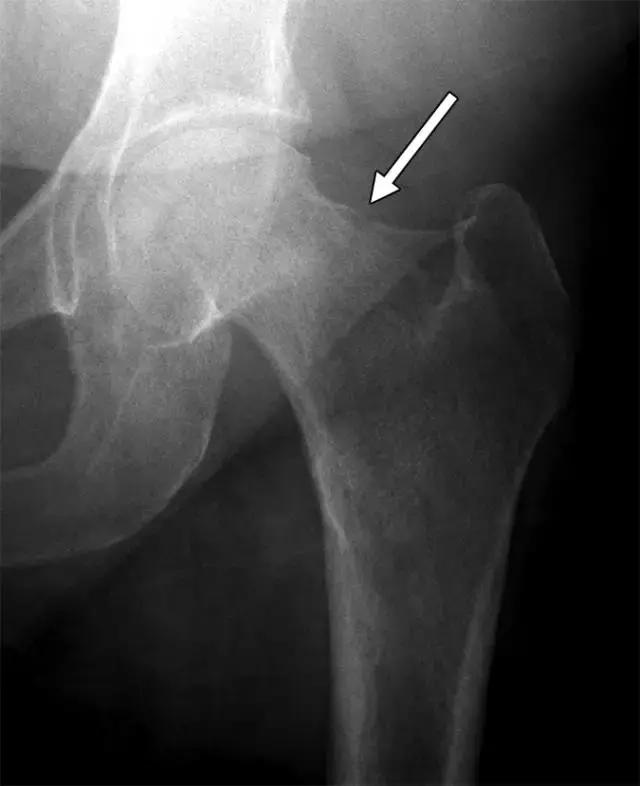

反向Segond骨折,是内侧胫骨平台的撕脱骨折,它是后交叉韧带严重受损的标志。这种骨折中的放射学检查结果与经典Segond骨折相似,只是反向骨折涉及胫骨近端的内侧(图6A)。据认为是由于内侧副韧带的深部荚膜组分的撕脱引起的(图6B),并且经常与内侧副韧带的严重损伤和相邻内侧半月板的周边损伤有关。

图6A -18岁的女性患有反Segond骨折。膝盖倾斜放射照片显示沿内侧胫骨平台的小撕裂性骨折(箭头)。

图6B,冠状脂肪抑制T2加权MR图像显示内侧胫骨平台内有明显的骨髓水肿,与内侧副韧带深部囊膜组分相关的反向Segond撕脱性骨折(箭头)。